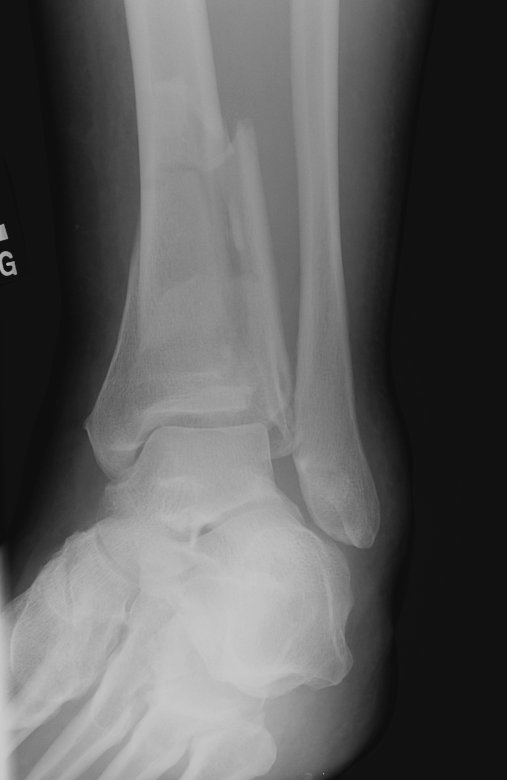

Return to Pilon Fracture